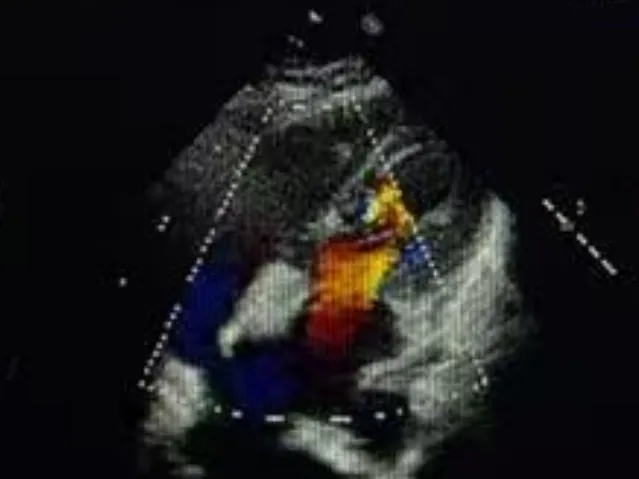

双封堵器释放后超声

心脏位于左侧胸腔,心尖指向左下。房室连接正常。右心较术前减小。左室壁不增厚,运动未见明显异常。主动脉瓣形态结构未见异常;二尖瓣形态结构未见异常;三尖瓣形态结构未见异常。

CDFI:AR(-),MR(少量),TR(少量)。房间隔中部探及两处封堵器回声,房水平未见明显分流。室间隔连续完整,室水平未见明显分流。肺动脉内径不增宽。升主动脉内径23mm。心包腔内未见明显液性暗区。

《常见先天性心脏病介入治疗中国专家共识》指出:对于存在2个ASD,但缺损间距≤7mm,可选择1枚封堵器闭合;多个缺损的间距>7mm,无法采用1枚封堵器实施介入治疗,需要选择2~3枚封堵器分别闭合[1]。本例食道超声示两处缺损(回声中断8.06mm,分流束宽5.63mm),两个缺损之间相距8.48mm,术中通过超声精准指导,先植入BDASD-I16封堵器封堵8.06mm缺损,再测量第二个缺损约5mm后,植入BDASD-I10封堵器,术后即刻超声显示,两枚MemoSorb可降解封堵器位置形态理想,无残余分流,封堵成功。